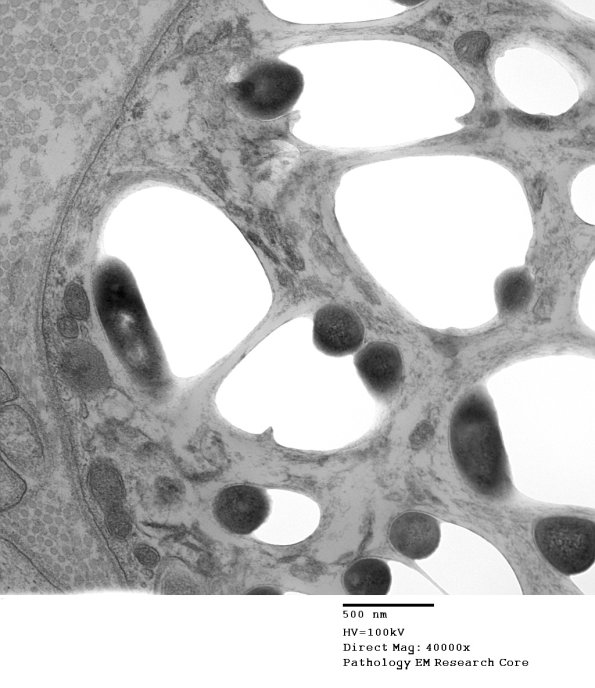

Electron microscopy shows the organisms as membrane bound round or rod-shaped electron-dense structures surrounded by a clear halo (possibly partially composed of bacterial metabolites and/or denatured host cytoplasmic components). (electron micrograph)